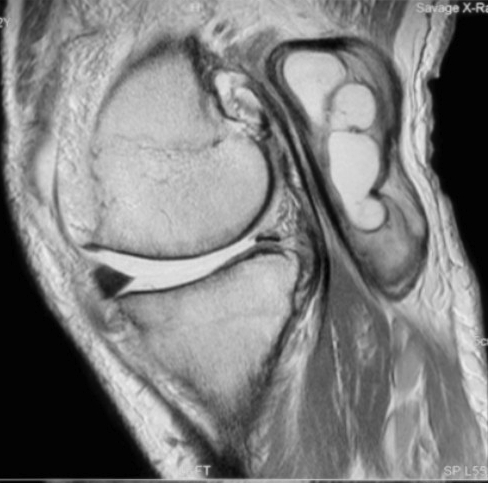

Baker cyst knee mri. A sports related injury or other blow to the knee can cause a bakers cyst. A bakers cyst also known as a popliteal cyst is a swelling that forms behind the knee when the tissue at the back of your knee fills with synovial fluid the lubricating fluid from the joint. A bakers cyst or a popliteal cyst occurs if there is an underlying intraarticular problem with the knee or and inflammatory reactions commonly as a result of losing bodies formed in conditions such as osteoarthritis rheumatoid arthritis gout acl tears meniscal tears or because of particles following knee arthroplasty mostly from the.

They represent neither a true bursa nor a true cyst as they occur as a communication between the posterior. Baker cysts or popliteal cysts are fluid filled distended synovial lined lesions arising in the popliteal fossa between the medial head of the gastrocnemius and the semimembranosus tendons via a communication with the knee jointthey are usually located at or below the joint line. Knee cyst is a fluid filled synovial fluid swelling that causes a lump around the knee area.

The pain can get worse when you fully flex or extend your knee or when youre active. This makes it swollen and inflamed. Synovial cysts meniscal cysts normal knee bursae and recesses have characteristic mr appearances.

Cystic lesions are common in knee mri and the commonest the bakers cyst has an incidence of 38. If the cyst breaks open pain may significantly increase with swelling of the calf. Cysts can vary in size and can very occasionally develop.